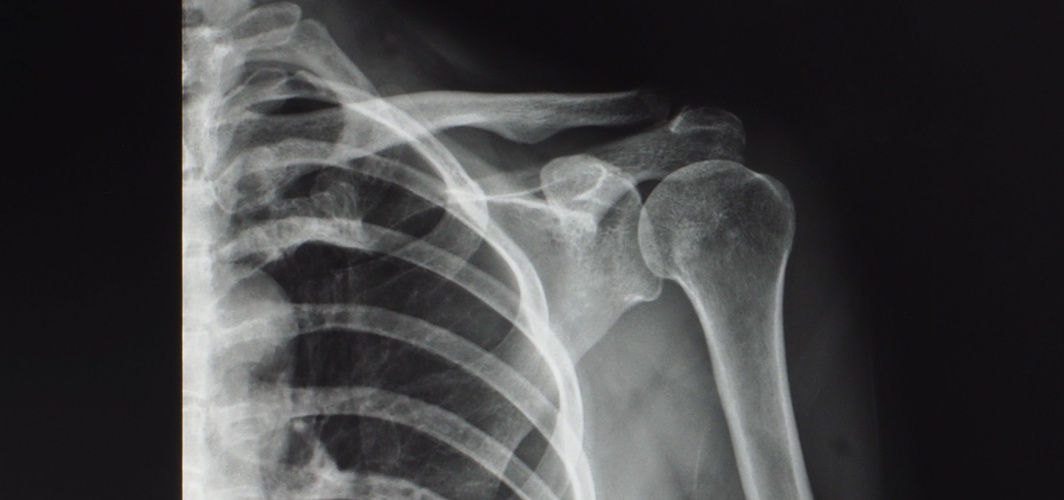

Imaging techniques such as X-rays, MRI scans and ultrasound may be used to aid in the diagnosis of shoulder conditions and determine the extent of the injury.

- X-rays